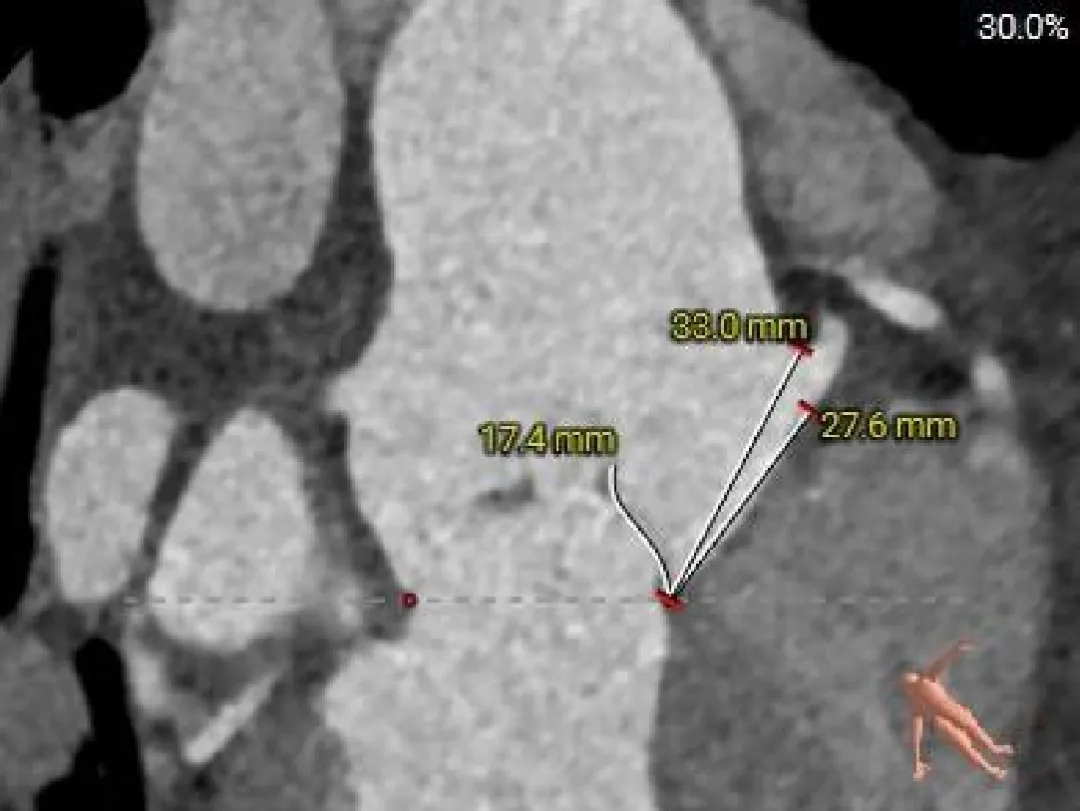

冠脉风险评估

Left Coronary

19.5mm

LCA & Leaflet

13.8mm<21.9mm

Right Coronary

18.3mm

RCA & Leaflet

17.7mm<19.7mm

-

左、右冠脉高度可

左右冠脉异窦

左、右冠瓣叶长度<冠脉开口下缘到窦底距离

结合SOV、STJ冠脉风险可控